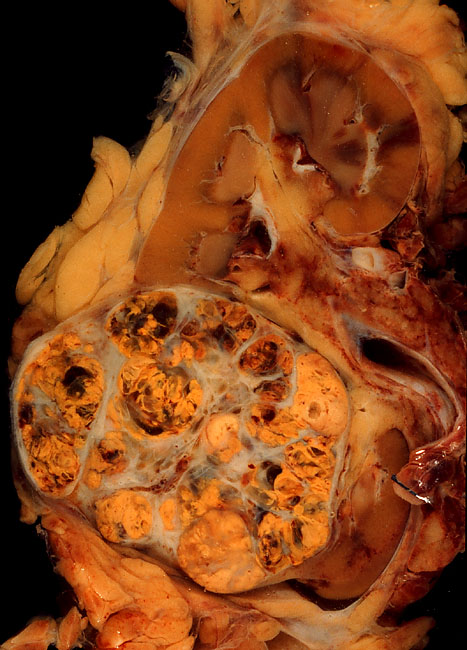

Рак почки – злокачественное новообразование, произрастающее из почечной ткани. Рак может поражать как одну, так и две почки одновременно. В структуре всех онкологических заболеваний рак почки занимает 2-3%.  Чаще всего заболевание поражает мужчин в возрасте 40-60 лет.

• при 1 стадии размер новообразования непосредственно в почке составляет в пределах 7 см в диаметре;

• на 2 стадии опухоль достигает размеров более 7 см в диаметре в пределах почечной ткани;

• на 3 стадии опухоль выходит за пределы почки в околопочечные ткани или крупные вены. Также поражается ближайший лимфоузел;

• при 4 стадии опухоль разрастается в соседние органы. Также образуются метастазы в лимфоузлах и прочих органах.